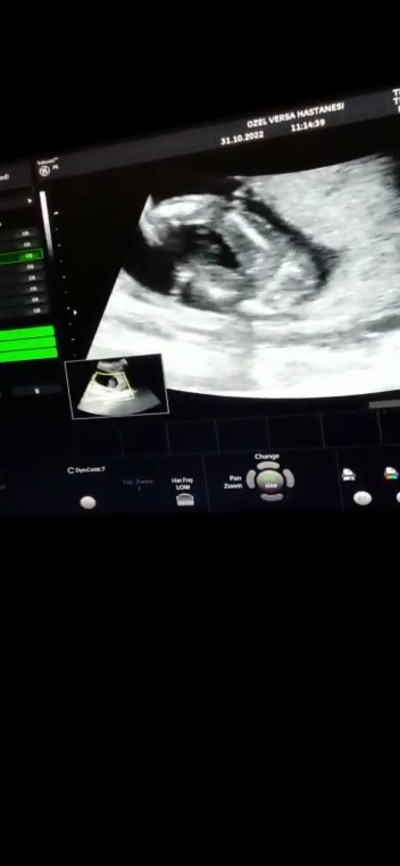

Hanimlar merhabaa bugün cinsiyeti öğrendik ama doktorumuz çok uğraştı kız gibi duruyor dedi anlayanlar bakabilirmi

Gebelik haftası 15+3

Aynen kemik yapısı kız kemik yapısı

16+2 de yani dün ki utrason benimki de kız canım bak